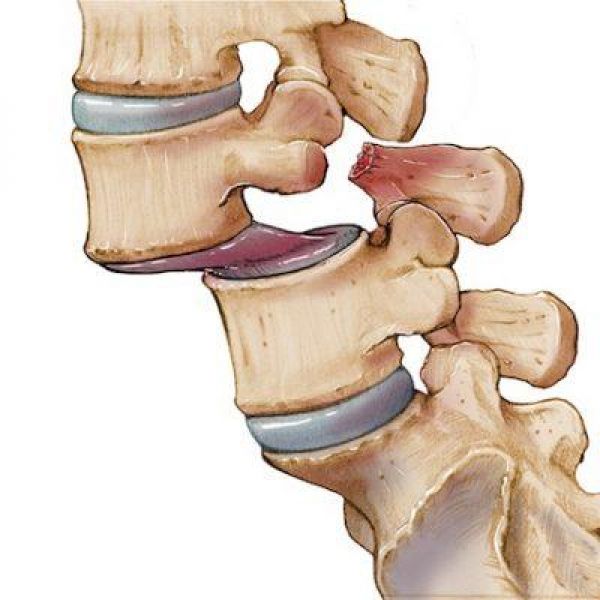

O termo espondilolistese é usado para descrever várias doenças da coluna onde uma vértebra escorrega saindo do alinhamento normal com a outra vértebra.

O termo espondilolistese é usado para descrever várias doenças da coluna onde uma vértebra escorrega saindo do alinhamento normal com a outra vértebra.

“Escorregamento de uma vértebra sobre a outra vertebral

“Escorregamento de uma vértebra sobre a outra vertebral